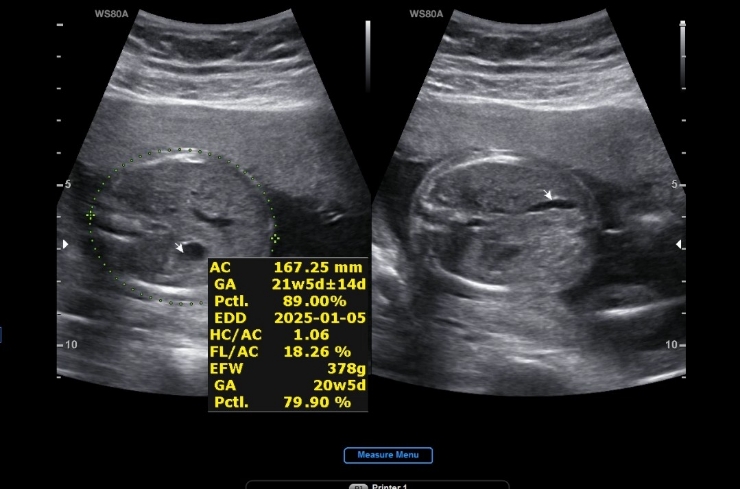

28w 1d 정기검진

2024.12.19

입체초음파 찍는날 세상에 첫째랑 완전 똑같 애기가 태반에 얼굴을 파묻고 있어서 보기가 매우 힘들었는데 ...